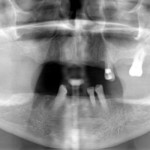

Este é um caso mais simples de se fazer e com um valor (custo-benefício) bastante cómodo.São somente 4 implantes na arcada inferior suportando uma barra sobre a qual será transferido em parte o esforço mastigatório. É confeccionada em RESINA como uma prótese total convencional.